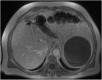

Isolated splenic cystic echinococcosis is a rare condition. In Greece the number of cases has declined substantially in the last 20 years. The spleen is the second most common extrahepatic site of cystic echinococcosis. Albendazole is safe, but mebendazole can be used as a substitute, in case of adverse reaction. Our patient was diagnosed with isolated splenic echinococcal cyst, during the investigation for newly diagnosed type 2 diabetes mellitus. We opted for elective splenectomy, based on a risk assessment due to the patient's working conditions, and treatment with albendazole represented a safety measure until surgery was possible. The patient developed acute hepatocellular injury to albendazole after eight weeks of treatment. This was confirmed through rechallenge with albendazole after discontinuation of the drug. Postsplenectomy the treatment with mebendazole proved to be safe with no adverse reactions. Even though, albendazole is known to be safe, monitoring of hepatic enzymes and full blood count should be offered. In case of toxicities, mebendazole with or without praziquantel can be used. Toxicity to mebendazole can be similar to albendazole but a trial is worthwhile. In our patient, treatment with mebendazole was uneventful.